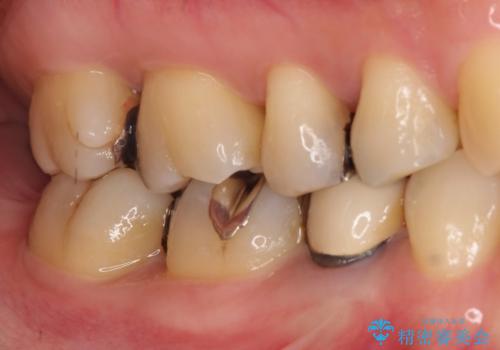

笑った時に見える金属を白くしたい

- 笑った時に見える金属を白くしたいとのことでメタルフリーの治療を希望され来院されました。

根管治療を行なったのち、オールセラミッククラウンにて修復処置を行っております。